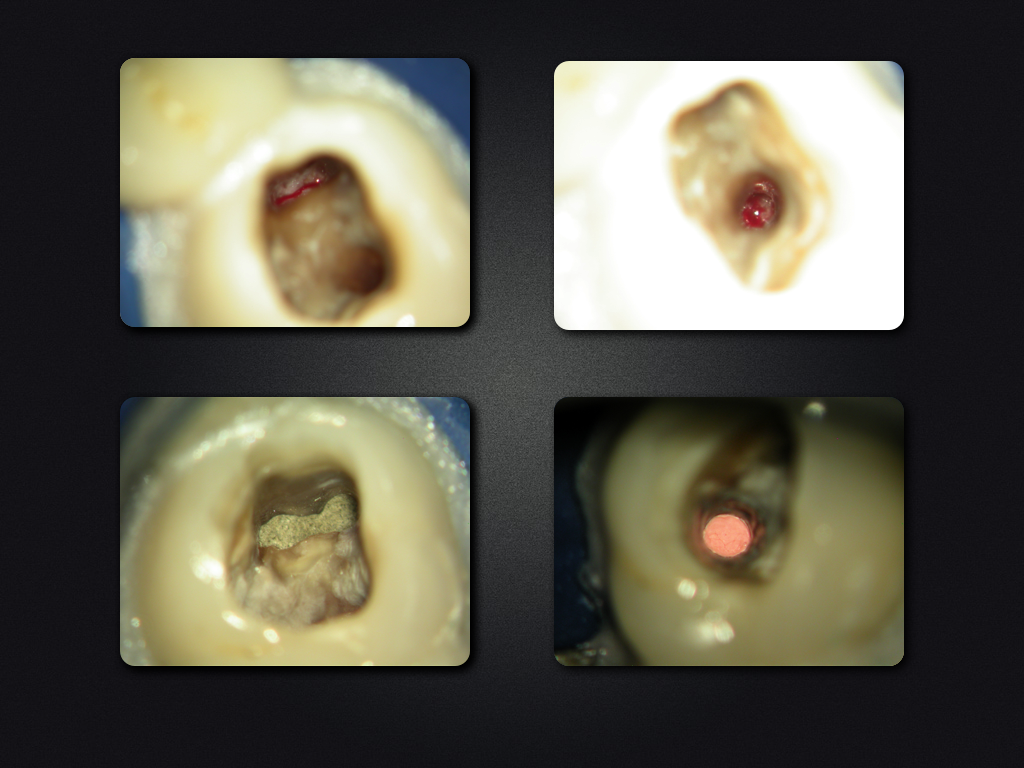

2D vs. 3D (XXVI)